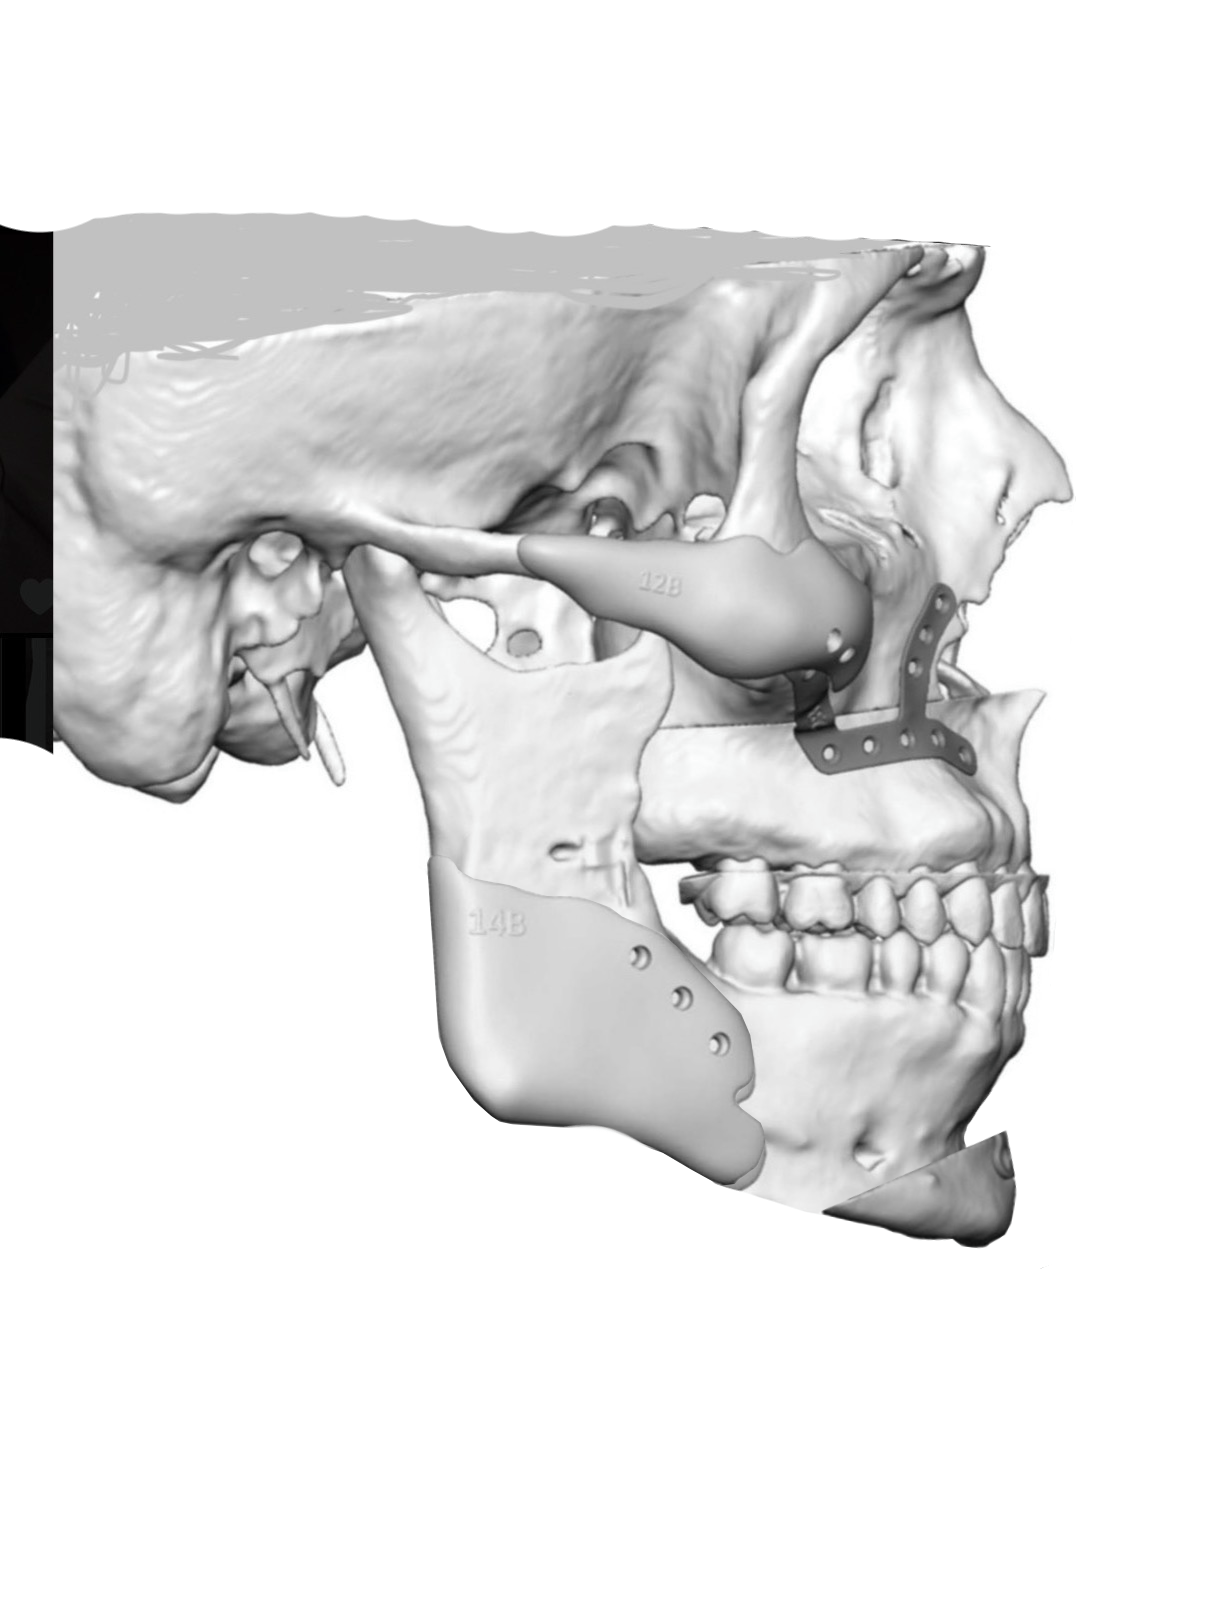

Getting a Le fort 1 with sliding genio to shorten my long face, replacing my jaw implants and adding cheek implants. Doing 6mm impaction with 4mm advancement. No BSSO. What do you guys think of the implant design? Angle too low? Attached pics are before and after